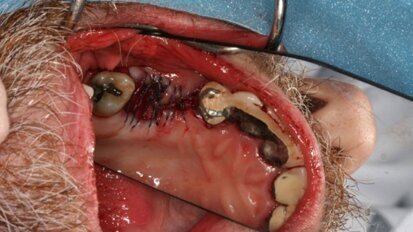

Implants migrés dans le sinus maxillaire

Comme prévu, la croissance des implantations dentaires a considérablement augmenté, ces dernières années. En ...